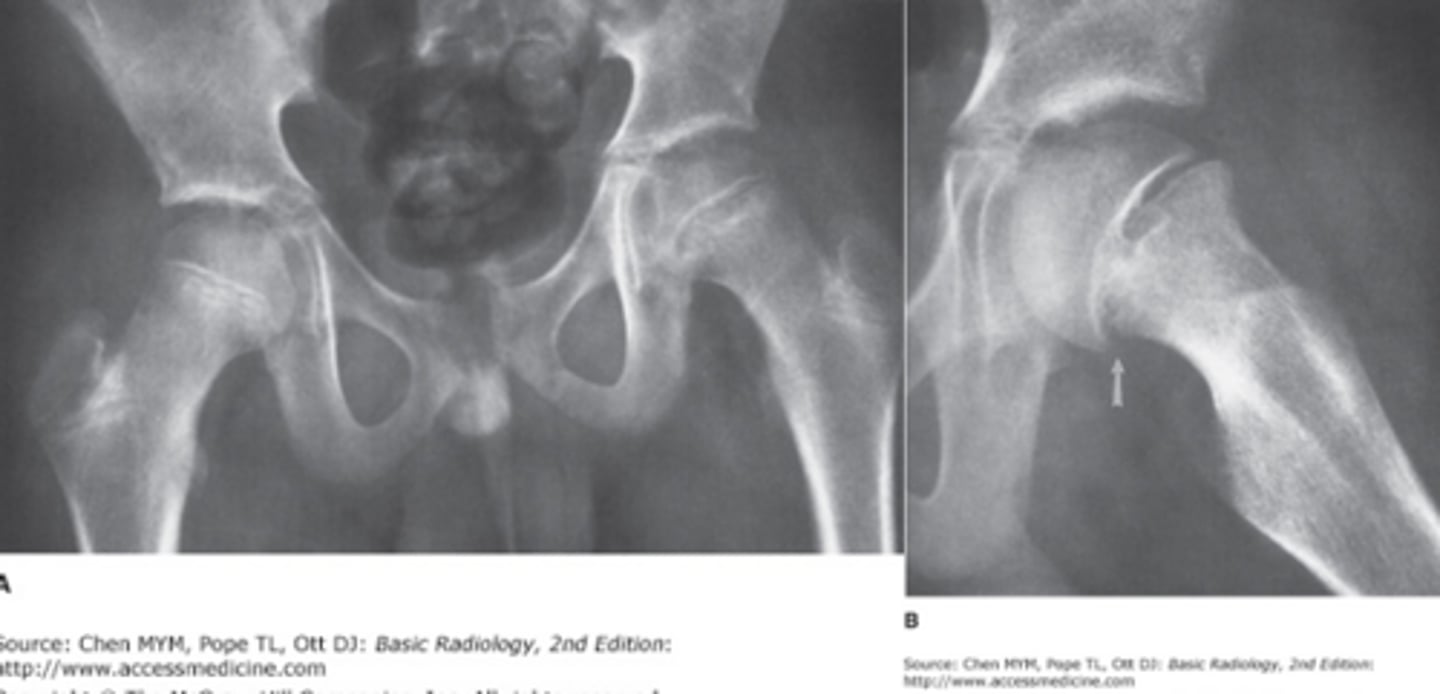

Look at this image and tell me what view and deformity

Analysis

Views: AP (left), frog leg lateral (right)

Analysis: Fracture through the physis of the left proximal femur. Lucent line demarcating the physis is slightly widened and alignment of the dges of the epiphysis and metaphysis is abnormal. Frog leg is more obvious. They have SCFE

Based on the two age ranges what do each of these individuals have respectively?

Answer

13-16 y/o: SCFE

5-8 y/o: Leggs Cathe Perthes

Leggs Cathe Perthes

Congenital AVN of the hip commonly in children around 4-8 y/o